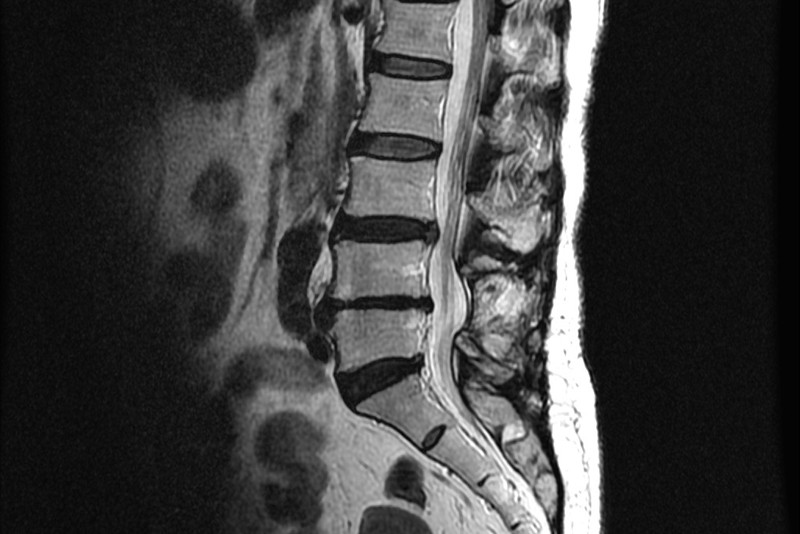

허리디스크의 증상은 허리 통증뿐만 아니라 다리로 내려가는 방사통은 많이 호소하는데 다리 저림, 감각 저하, 근력저하도 나타날 수 있습니다. 디스크의 바깥쪽을 이루고 있는 섬유륜이 찢어지면 디스크의 중앙 부분인 수핵이 찢어진 틈새로 튀어나오게 되는데 이는 디스크가 탈출한 것이고 흔히 디스크가 터졌라고 합니다. 디스크 탈출은 나이가 들면서 나타나는 섬유륜의 퇴행성 변화가 관련이 깊고 허리를 비틀거나 갑작스럽게 숙이는 동작, 외부로부터의 충격으로 인한 외상으로 인해 주로 나타납니다.